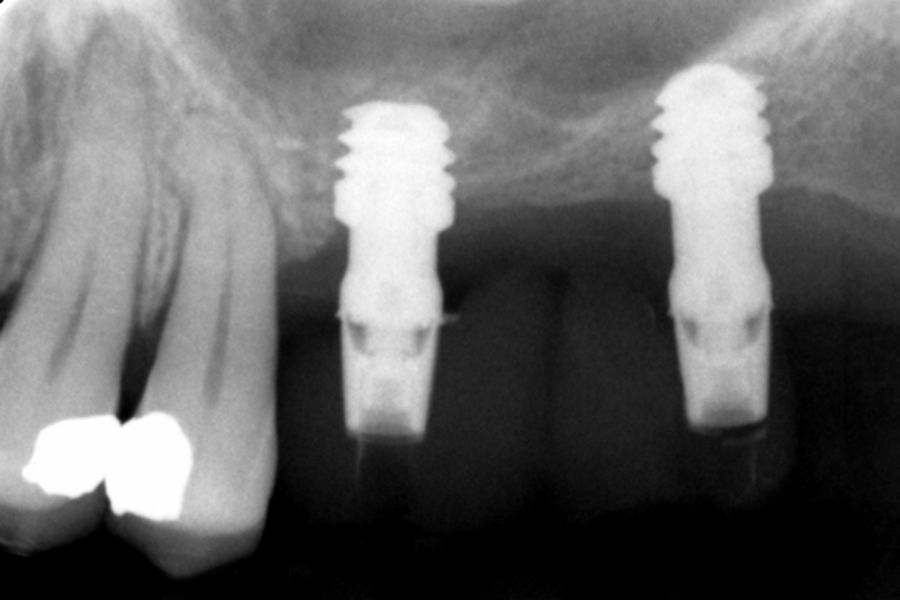

Figures 2-19 show one of the cases included in the study.

All implants were rehabilitated in two phases and all of them were ferulized to other implants in the rehabilitation. In all cases, screwed prostheses of more than one implant with intermediate elements (transepithelial) were performed, ferulizing to other implants with a length of 4.5 or 5.5 mm. In all situations, a progressive prosthesis load was carried out 6 months after insertion of the implant consisting of a provisional structure finished in resin to move to a definitive metal-ceramic prosthesis. In all cases, the initial transepithelial are preserved to maintain the hermeticity achieved in the first phase of prosthesis manufacture.

Ten patients who met the inclusion criteria were recruited, in which 20 implants were inserted. Three of them were women with an average age of 72 (+/- 6 years). None of the patients were smokers at the time of surgery and did not have any active periodontal disease. The majority of the implants diameter included in the study was 5 mm (60%), followed by 4.5, 5.5 and 4.75 mm (13.33% each). The predominant length was 5.5 mm (86.6% of the cases), with 13.4% of the remaining implants with a length of 4.5 mm. The most common positions were for the second molars (molars 27 and 17) representing 55% of the cases.

The mean height of the residual bone volume was 3.1 mm (+/- 0.3 mm with a range of 3-4 mm). In all cases, transcrestal sinus elevation was performed, with particulate autologous bone obtained from milling the neo alveolus generation zone for implant insertion, being the average of this elevation above the apex of the implant of 2.8 mm (+/- 0.99 range 1.9 -5 mm). In the CT control scan after one year of inserting the studied implants, the bone gain achieved was maintained, no decrease in the volume gained was observed, only three cases showed a decrease of between 0.4 and 0.5 mm of the initial volume at the end (Table).